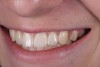

Fig 21. Smile view.

Figure 21